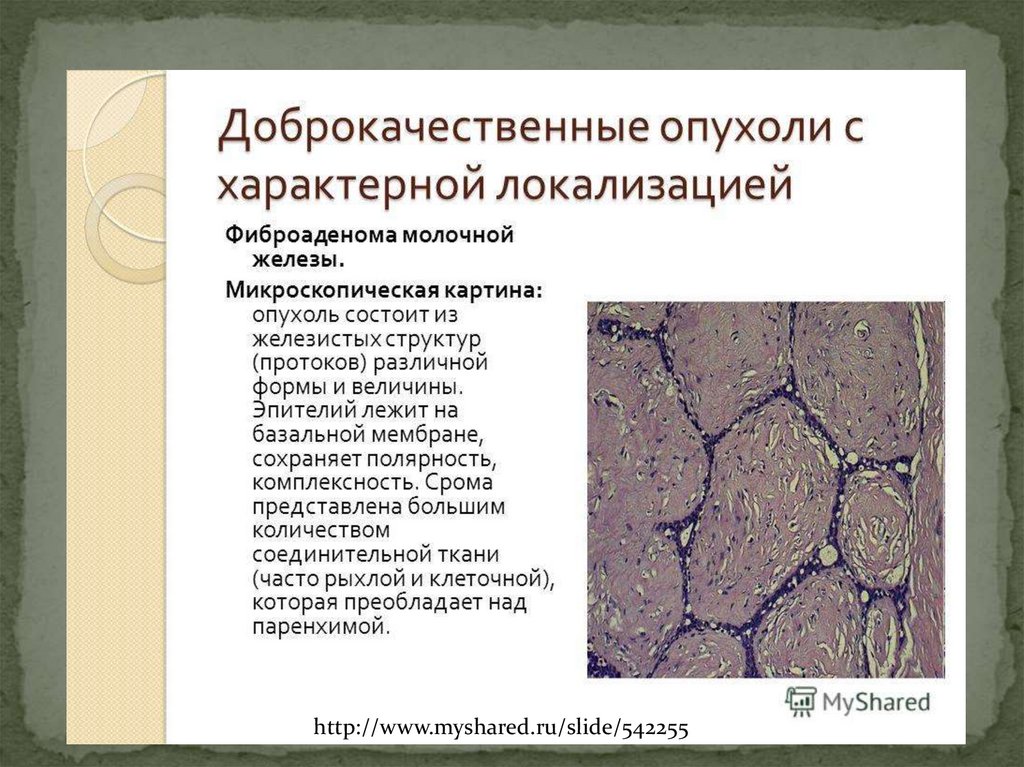

Новообразование в головном мозге. Презентация опухоль мозга. Опухоли головного мозга презентация. Злокачественная фиброаденома молочной железы. Фиброаденома молочной железы Размеры для операции. Фиброаденома молочной железы маммография. Листовидная опухоль гистология.

Злокачественная фиброаденома молочной железы. Фиброаденома молочной железы Размеры для операции. Фиброаденома молочной железы маммография. Листовидная опухоль гистология. Доброкачественная опухоль. Доброкачественныеопкхоли. Клетки, образующие доброкачественную опухоль:. Строение доброкачественной опухоли.

Доброкачественная опухоль. Доброкачественныеопкхоли. Клетки, образующие доброкачественную опухоль:. Строение доброкачественной опухоли. Гиповаскулярные метастазы печени кт. Опухоль желудка метастазирование.